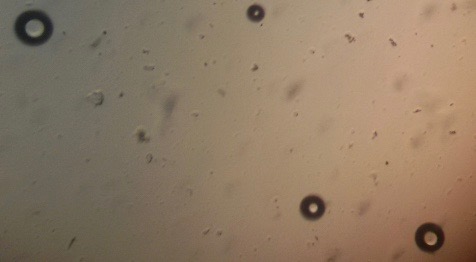

Preparation of niosomes from proniosomes and morphological evaluation (Photomicroscopy)

The optical photographs of all reconstituted proniosomal formulae are shown in fig. (1-28). The photographs revealed that the formed niosomes are unilamellar vesicles with a spherical shape and smooth surface. The vesicles were insular and separate without aggregation or lumping. Apparently, proniosomal formulae containing span 40 and span 60 yielded vesicles of large numbers with well-identified outline and core which will affect the entrapment efficiency of loaded drug directly. However proniosomal formulae containing span 20 and span 80 produced small numbers of vesicles with a slightly different outline. This may be due to the high phase transition temperatures of both span 40 and span 60 which will cause the formation of a large number of stable niosomal vesicles. The phase transition temperatures for span 20, 40 and 60 are 16, 42 and 53 °C; respectively, however, span 80 possess the lowest phase transition temperature at 12 °C [35]. This explains why proniosomal formulae containing span 20 and span 80 produce small numbers of vesicles upon hydration.